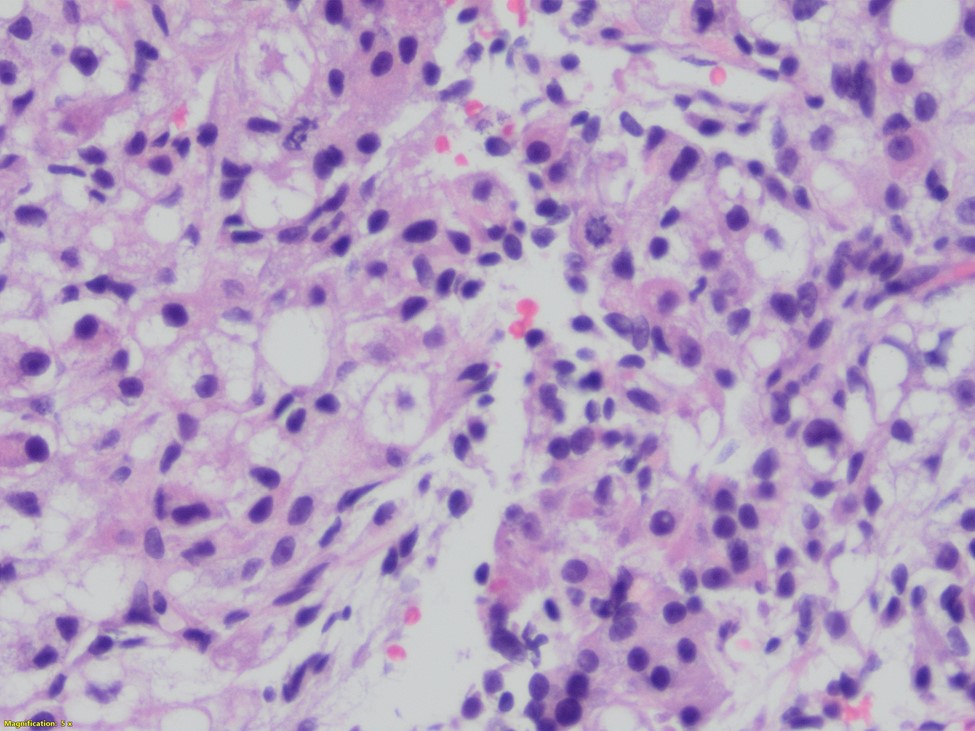

This unusual biphasic tumor has both carcinomatous and spindle cell component. The carcinomatous component is formed of granular, clear and markedly anaplastic cells. In some areas, the architecture recapitulates parathyroid differentiation: chief cells and oxyphil cells-like clusters. The areas that are poorly differentiated shows spindle and clear cell component. Keratin stain demonstrated the biphasic nature of the lesion. The tumor is positive for synaptophysin, and negative for calcitonin, Pax8, TTf-1, Sox10, and HMB45. Based on these immunostains and focal parathyroid differentiation a diagnosis of carcinoma with sarcomatoid features favoring parathyroid origin was rendered.